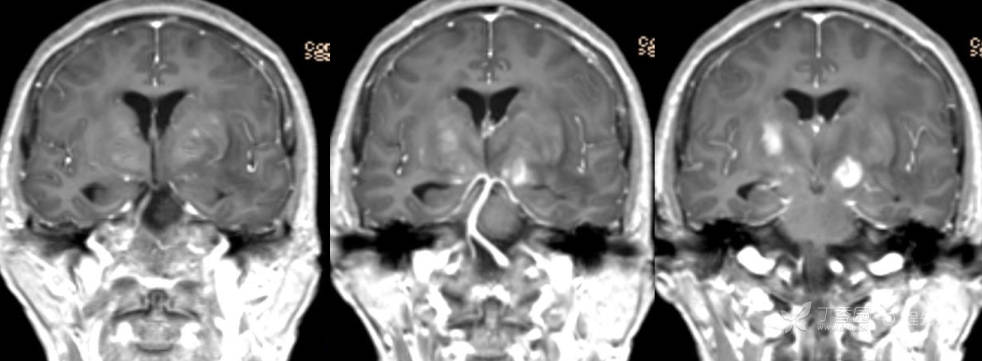

2月特别精彩病例|头晕伴言语含糊1月,梅毒患者的颅内占位你如何考虑?【病理已公布】

主诉:头晕伴言语含糊1月。

梅毒TRUST血清实验(TRUST):1:32阳性(+)

梅毒特异性抗体凝集试验(TPPA):阳性 (+)